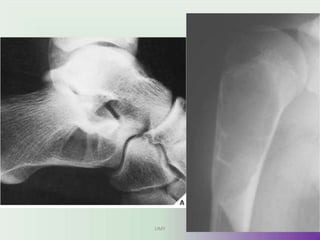

Osteochondroma

• Clinically,

osteochondromas

present as slow-growing

masses, which can be

painful if they impinge

on a nerve or if the stalk

is fractured. In many

cases, they are detected

as an incidental finding.

Osteochondroma. On this lateral view of the ankle, a

benign osteochondroma is seen projecting posteriorly

on a stalk. The end (arrows) is often covered with a

cartilaginous cap. These lesions always occur near a

UM

jo

Yint but point away from it.